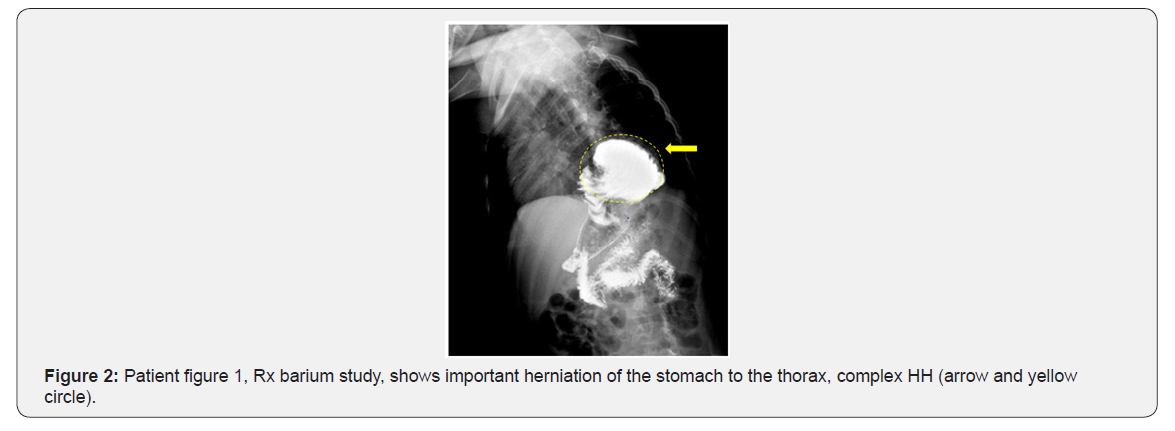

suspected by the presence of one or more of the following symptoms and signs: vomiting, regurgitation, heartburn, epigastric pain, dysphagia, coughing and wheezing, pneumonia, life-threatening events (apneic spells), among others, and confirmed with upper GI tract X-Ray (Figure 1 & 2), endoscopy, and in some cases impedance-pH measurement.

The diversity of transoperative surgical findings that caused the failure are: HH, wrap disruption, slipped wrap, crural stenosis, twisted wrap, and misplaced wrap, being the most frequents: HH, slipped wrap and misplaced wrap [68]. Our findings in relation to these, coincide with that reported in other series, HH and/or partial or total slepped wrap.